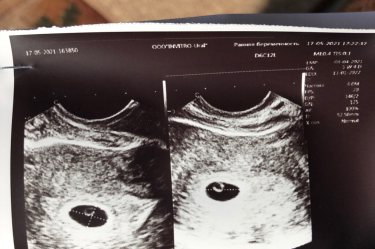

Девочки, всем привет 🙋‍♀️ недавно со мной случилось счастье! Я узнала, что беременна и беременность первая. Столько разных эмоций и новых ощущений, сейчас у меня подходит 6 акушерская неделя, стараюсь себя не накручивать, но все же всегда переживаю если тянет живот (хотя знаю, что это норма) или же немного побаливает поясница, пока что токсикоза нет, но может быть ещё рано, а может я просто везучая 😉 на учёт пока что не встала, но планирую в ближайшее 2 недели. Сегодня решила сходить в платную клинику на узи, что бы удостовериться, что беременность маточная и что все протекает хорошо. И вот долгожданный снимок у меня в руках 😍 врач узист сказал, что все протекает в норме по сроку, но я немного напугалась, т.к не увидела эмбриона 😥 плодное яйцо и желточный мешочек есть, а вот моего червячка не видно, сказали, что вскоре должен появится, скажите пожалуйста у кого был такой же снимок на 5,5 неделе??

И у меня на 5 неделе не увидели,только плодное яйцо и желточный мешочек был, а эмбриона не было видно, на что врач сказал, что ещё рано, появится). И вот недавно сделала УЗИ, по показанию врача, и уже видела как бьётся сердечко у нашей креветочки ? НЕ переживайте, Всему свое время ?

Да, было в 5 нед тоже самое. В 7 нед увидели «червячка»

У меня так же в 5недель узи показало. Эмбриом увидели и сердечко прошлушали в 7недель